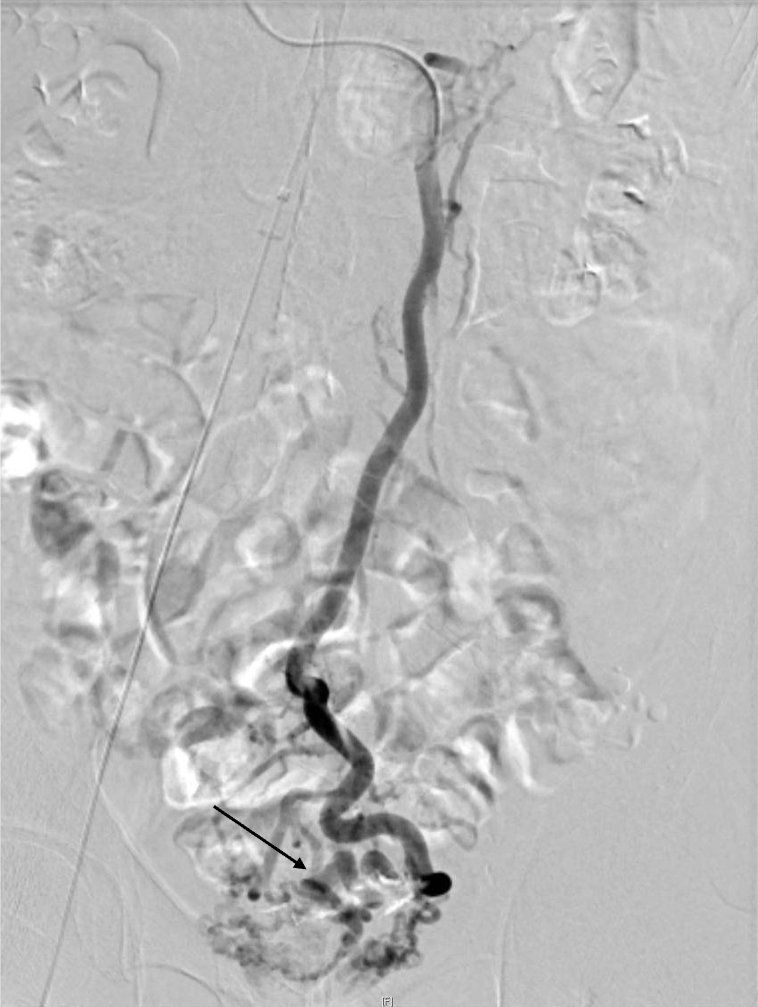

直腸静脈瘤の破裂予防目的にヒストアクリルを用いた経皮経肝的静脈瘤塞栓術を施行した。治療一か月後の治療効果判定に撮影を行った。

肝硬変のスクリーニング目的の造影CTにて直腸静脈瘤が判明した。破裂予防目的に経皮経肝的静脈瘤塞栓術を施行した。術前CTにて血管解剖を把握の上、治療を行った。術後一か月の造影CTにて、標的血管の良好な閉塞が確認された。

当該疾患の診断における造影CTの役割

直腸静脈瘤を始めとする異所性静脈瘤においては、IVR治療が選択されることが多い。術前に正確な解剖の把握が必要であり、造影CTの果たす役割は大きい。特に門脈系の良好な描出が求められ、適切な時相での撮影が肝要である。撮影後thin slice軸位断像での観察、任意多断面再構成像(MPR)やVolume rendering画像(VR)で評価を行い、術中のガイドとする。また肝細胞癌を併発することが多い為、動脈優位相における撮影も行う必要があり、dynamic studyを要する。治療においてはヒストアクリルや金属コイルなどのアーチファクト源となり得るデバイスが使用されるため、必要に応じてmetal artifact除去を活用する必要がある。また別部位に新たな静脈瘤が生じたり、腹水などの門脈圧上昇に伴う所見や門脈血栓などの合併症が生じる危険性があるため、造影CTによる評価が重要である。

CT技術や撮像プロトコル設定について

本症例においては、腎機能障害や心不全など、特段併発症を有さない患者様であったため、標準的な撮影プロトコルで撮影を施行した。管電圧は120kVを使用し、逐次近似併用(ASiRV 20%)で再構成を行った。また造影については、536mgI/kgの投与とし、固定法(動脈相 35秒、門脈相80秒後、平行相180秒後)で撮影を行った。ただし肝硬変患者においては、腎機能障害を有することがしばしばあり、その場合には造影剤減量が必要となる。従って低管電圧撮影や逐次近似再構成法、dual energy CTを使ったvirtual monochromatic imageなどを適宜活用する必要がある。また金属コイルなどによる血流改変を施行した場合には、metal artifact除去などを併用して評価を行う必要がある。加えて肝肺症候群などに起因する心機能障害を有することがあり、その場合には固定法による撮影ではなく、bolus tracking法などを活用した撮影が必要となる。